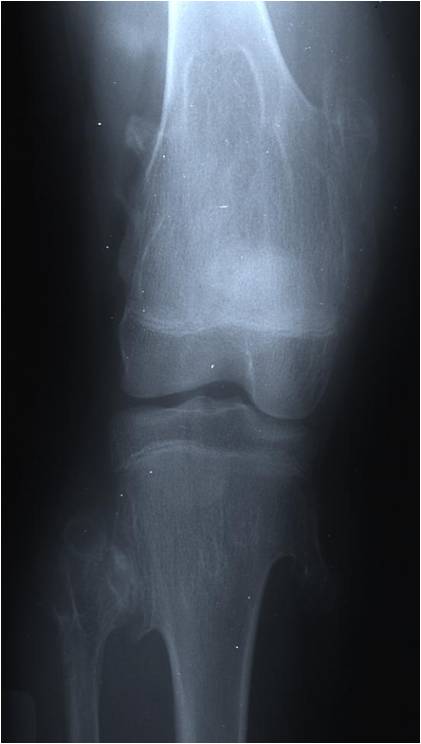

Radiographic Presentation

Plain X-rays:

- Projects from bone with narrow (pedunculated) to broad (sessile) stalk

- Corticomedullary continuity: Medullary bone continuous with that of osteochondroma and cortex blends with that of osteochondroma

- Calcification in cartilaginous cap (“Ring and Arc” and stippled calcifications)

- Lobular growth pattern

- Long bones: arise from metaphysis, grows away from epiphysis toward diaphysis,

- May be associated with failure of tubulation in Multiple Hereditary Exostosis

Multiple Heredity Exostoses (MHE)

- Radiographically characterized by multiple osteochondromas and undertubulation of bones

- (Erlenmeyer Flask Deformity)